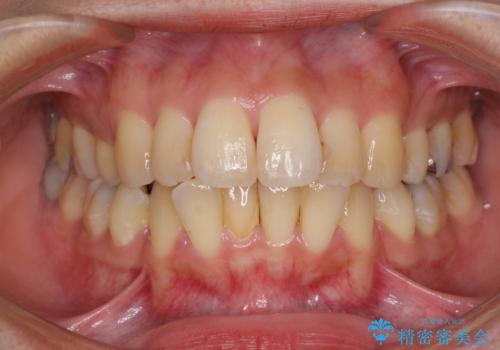

[ 先天性の前歯欠損 ] 矯正とインプラントの包括治療

![[ 先天性の前歯欠損 ] 矯正とインプラントの包括治療の症例 治療前](https://seimitsushinbi.jp/wp/wp-content/uploads/2022/12/3fbbdf32ff659566fa6c202e2fa05e30-500x350.jpg?v=1671606172)